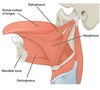

Suprahyoid musucles

- digastric

- geniohyoid

- stylohyoid

- mylohyoid

Digastric

ACTION: depress mandible; elevates hyoid during swallowing

ATTACHMENT: Anterior and posterior bellies, from the digastric fossa of the mandible and the mastoid notch of the temporal bone to the intermediate tendon to body and greater horn of hyoid bone

INNERVATION: CN V/anterior belly,CN VII/posterior belly

**suprahyoid ms**

Geniohyoid

ACTION: depress mandible; elevates hyoid

ATTACHMENT: from the inferior mental spine of the mandible to the body of the hyoid

INNERVATION: C1 via CN XII

**suprahyoid ms**

Stylohyoid

ACTION: draws hyoid posteriorly & elevates it

ATTACHMENT: superior to post belly digastric, from the styloid process of the temporal bone to the body of they hyoid, superior!!!

INNERVATION: CN VII

**suprahyoid ms**

Mylohyoid

ACTION: elevates hyoid and floor of mouth

ATTACHMENT: mylohyoid line of the mandible and the mylohyoid raphe on the body of the hyoid one. , makes up floor of mouth

INNERVATION: CN V3 = mandibular br. of trigeminal n.

**suprahyoid ms*